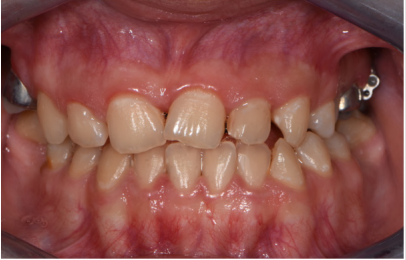

A female patient presented in our office for a consult. Her oral hygiene status needed improvement especially in the frontal upper area. Intraoral photographs reveal that in the transversal plane she had crossbite contacts between all the teeth and severe discrepancy between and the midline of the face the upper arch midline which was deviated to the right with almost the size of a lower incisor. In the sagittal plane she had canine class III on the right side and class I on the left side due to the rotated mandibular left canine and end to end to inverse overjet in the anterior region (Figures 3 & 4) and in the vertical plane, she had 1 to 2 mm of inverse overbite and bilateral open bite. Her upper right maxillary molars were absent and she presented moderate crowding in both upper and lower arch. The steps in the treatment plan were to expand the maxilla with the aid of a Hybrid Maxillary Expander followed by fixed appliances on the both Arches. In this case report, we present the results after the expansion of the maxilla and the processes that needed to be followed for the fabrication of the Hybrid Maxillary Expander. The first steps in the digital planning were clinical examination and intraoral scanning. The patient was referred to a radiological center for a CBCT. The intraoral scan and the CBCT were sent to the laboratory and analyzed for the implant planning. The mini screws were planned to be inserted in the anterior part of the palate, paramedian, this being an optimal area that has lower variability of bone thickness, a thinner mucosal layer and a lower density of blood vessels compared to the other [9].

At the end of the expansion period, the anterior and posterior crossbite was solved and in the vertical plane, the lateral open bite had clearly improved. The upper jaw from the occlusal view has visible changes in its transversal dimension and space was gained, proof being also the diastemas that appeared between all teeth not only the median one. After the expansion, the patient will wear edgewise appliances for correction of the crowding, the interincisal midlines and for detailing and stabilizing the occlusion (Figures 9-11).